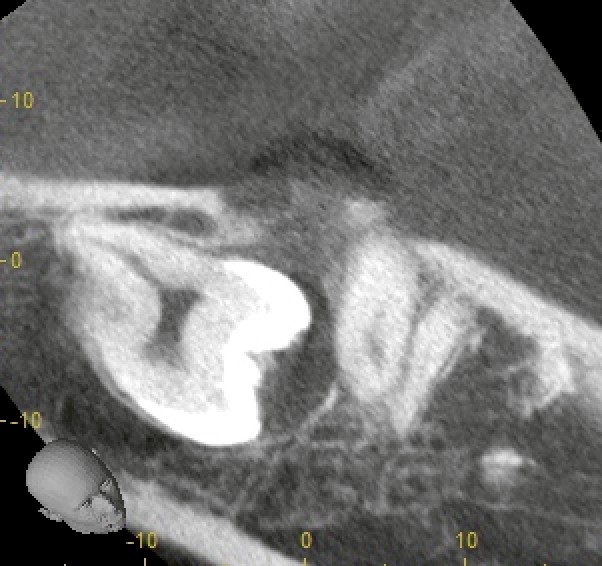

CTで分かった「見逃せない所見」

そこでCTを撮影し、三次元的に位置関係を詳しく確認しました。

すると、埋伏した親知らずの歯冠周囲に、はっきりとした透過像(黒く抜けて見える部分)が認められました。

この透過像は、嚢胞(のうほう:袋状の病変)である可能性が高い所見です。病名としては、臨床的には「含歯性嚢胞」が疑われる状況でした。

嚢胞を放置すると、徐々に拡大して骨が薄くなったり溶けたりし、手前の歯や下顎骨へ影響が出ることがあります。

今回の「圧迫感」は、この嚢胞性変化が関係していた可能性も考えられました。